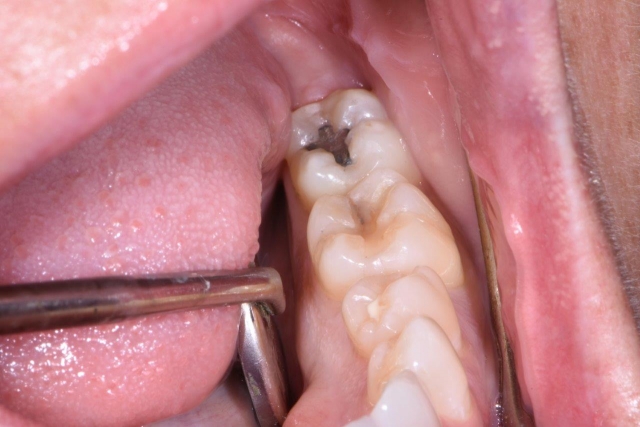

Many times, cracks/fractures are found in teeth on a daily basis in the restorative practice, especially after removing an existing restoration, having little to no symptoms. This can be described as an incomplete fracture if it involves one marginal ridge and a complete fracture if it involves both marginal ridges. It is a silent situation until the fracture worsens.

If your patient comes in with no symptoms, how and when can you tell if a tooth is cracked without symptoms? First and foremost, magnification and visualization are key components. How much magnification? Often in general dental practices, we utilize loupes up to six times magnification along with intraoral cameras to help see and diagnose cracks, but 13 times is the minimum needed to seek cracks/fractures visually.2,3 It has been shown that we can also use staining such as with methylene blue in addition to magnification to help identify cracks.4

We can also use a high-intensity, focused light for transillumination to help us visualize incomplete fractures/cracks in teeth. Without proper magnification and other techniques (use of a surgical operating microscope, which is found on a regular basis in most endodontic practices), and with no symptoms present, fractures in teeth can be challenging to visualize and/or identify and subsequently, to treat appropriately.

Visually, we have to be observant of our patients and look for wear facets, cracked restorations, hypertrophy in jaw muscles, and other missing teeth, craze lines, etc. We also must do an examination that ideally reproduces the symptoms that the patient is experiencing, but also know that just because we can’t reproduce the symptoms, it does not mean the tooth is not cracked. We need to do an examination looking closely at the area in question, as well as exploring the tooth in a tactile way for any “sticks,” pain or irregularities of the tooth surface. This can be done by variety of methods, including bite tests (a Tooth Slooth is a nice tool to use and isolate individual cusps/teeth), vitality testing, magnification, transillumination, visual and tactile examination, periodontal probing for isolated pockets, radiographic examination, including CBCT 3D exams, and even removal of an existing restoration.